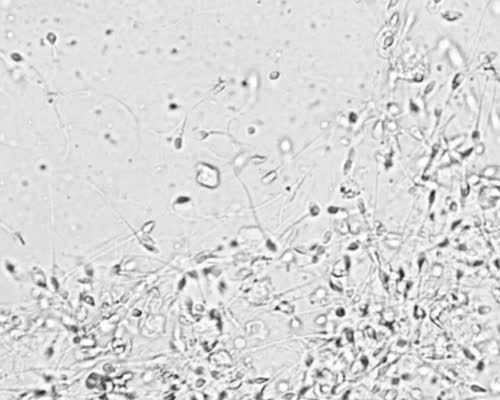

厦门市妇幼保健院的试管婴儿技术是不错的,这家医院做试管婴儿的成功率可以达到40%到50%左右,比较高的状态还可以达到60%左右。不过现目前厦门妇幼还没有开展第三代试管婴儿技术,厦门市妇幼保健院现目前开展的辅助生殖技术是夫精人工授精、供精人工授精、一代试管婴儿和第二代试管婴儿,虽然该医院目前还做不了三代试管,但是厦门妇幼生殖中心在2026年就顺利通过专家评估,获准筹建第三代试管婴儿技术项目,相信不久后该医院就可开展三代试管技术了。

厦门市第一医院生殖医学中心筹建于2009年,成立于2011年,总面积约1300平方米,仪器设备投入约1200万,位于省内同类科室前列。我院生殖医学中心是闽西南首批获准开展辅助生殖技术资质的地方医疗机构,开科以来完成了多项闽西南首例的辅助生殖技术的衍生技术,取得了不少科研成果,并在业界具有一定的影响力。

医院信息医院简称厦门市第一医院医院全称厦门大学附属第一医院成立时间1937年院长姜杰医院等级三级甲等医院地址福建省厦门市思明区上古街10号现目前生殖中心可以开展的技术有夫精人工授精技术、常规体外受精-胚胎移植技术、卵胞浆内单精子显微注射技术、胚胎冷冻及冻融胚胎复苏移植、促排卵助孕、妊娠保胎、生殖健康及其保健等。